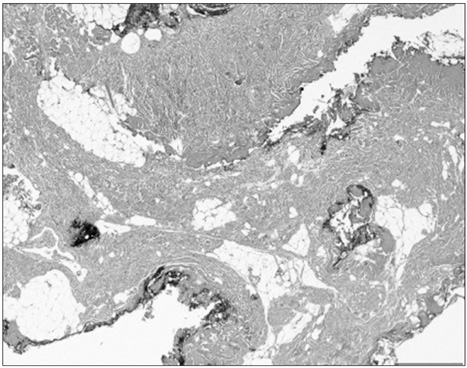

Fig. 3

Microscopic finding of specimen; dense collagenous tissue with balnd spindle cells and adipose tissue (H&E, ×40).

Fig. 3 Microscopic finding of specimen; dense collagenous tissue with balnd spindle cells and adipose tissue (H&E, ×40).